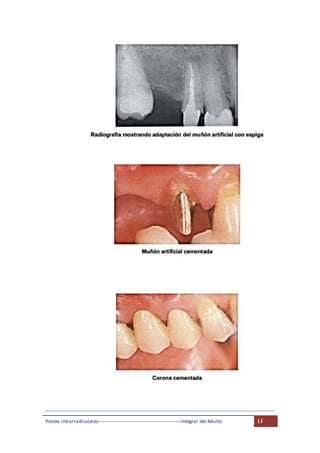

Vista de un segundo premolar superior y un segundo molar superior que

serán preparados para prótesis fija y la radiografía, en el cual recibirá un

muñón artificial con espiga.